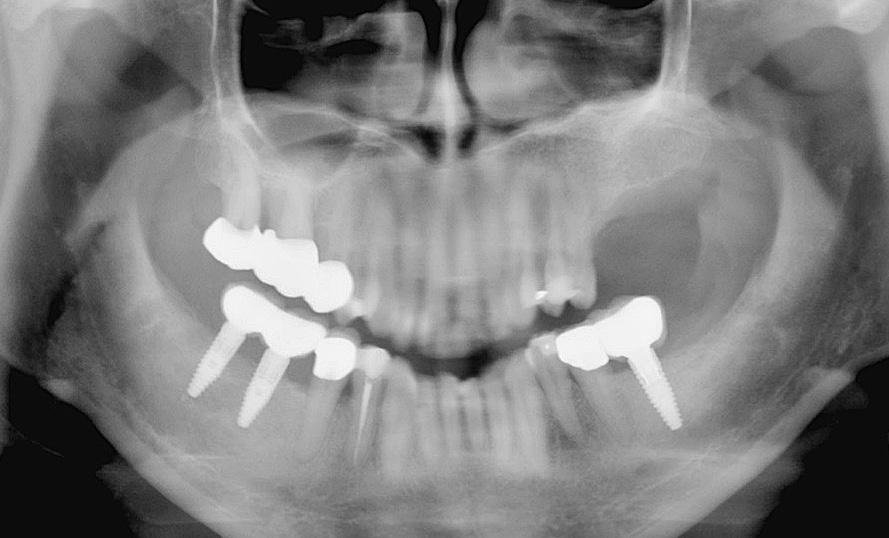

5. ábra: A kontroll röntgenfelvételen látszik, hogy az ideiglenes titán bázis gingivális magas sága túl alacsony, subcrestalis behelyezés esetén érdemes magasabbat választani.